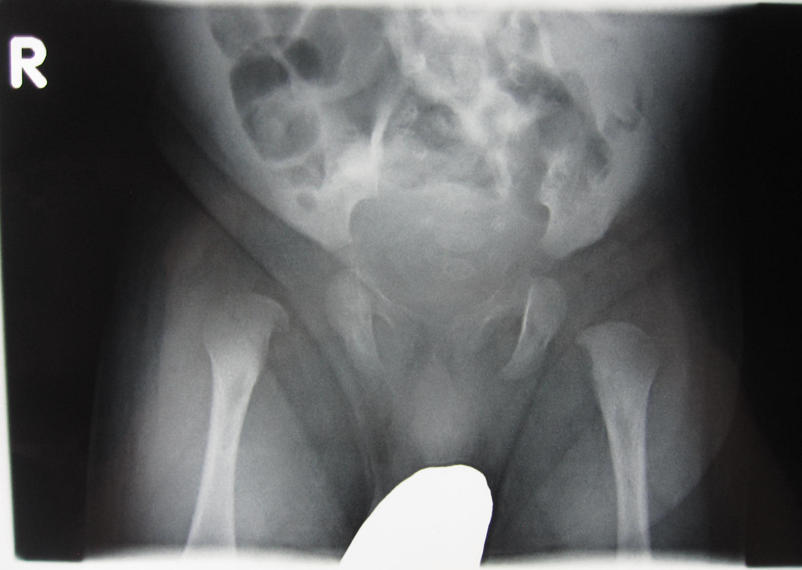

単純X線像

右化膿性股関節炎 (1か月、男児)

骨頭は未骨化のため観察できないが、右股関節の外方化がみられ、ほぼ脱臼位となっている。